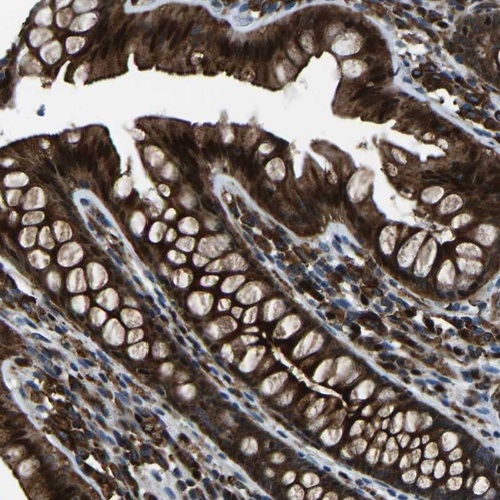

Immunohistochemical staining of human colon shows strong cytoplasmic and nuclear positivity in glandular cells.